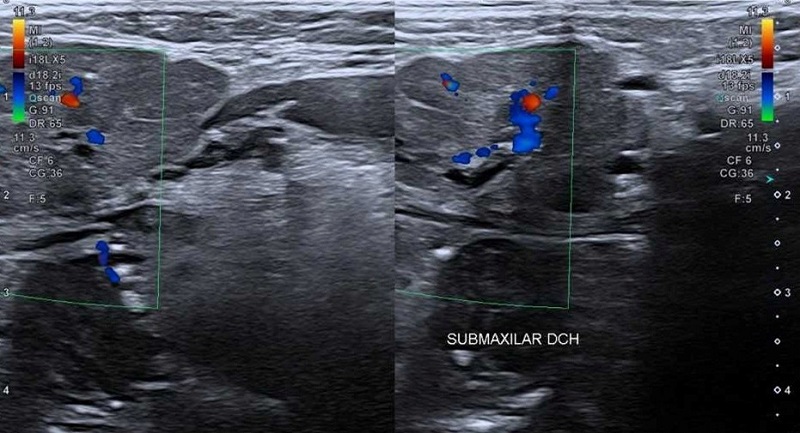

En la ecografía se visualizó una submaxilitis derecha (Figura 2), de probable origen litiásico dados los hallazgos indirectos (dilatación de conductos intraglandulares y conducto de Wharton), sin poder visualizar ecográficamente la litiasis.

Figura 2. Submaxilitis derecha